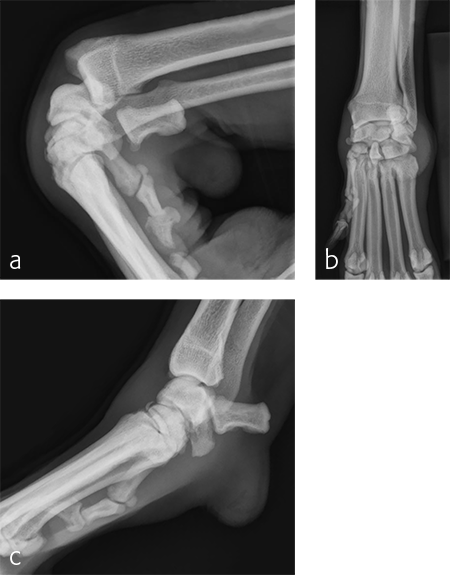

A 7-year-old, 32.5 kg, Labrador Retriever became acutely lame on the left thoracic limb while catching a ball. It was evaluated three weeks later and had carpal swelling, pain, and instability of the left carpus. Flexed lateral, craniocaudal, and extended mediolateral view images of the left carpus revealed a dorsal chip fracture at the carpometacarpal joint and hyperextension of the left carpus (Fig 9).

Treatment with a splint for several weeks resulted in no improvement. A pancarpal arthrodesis was performed with the 2.7/3.5 Pancarpal Arthrodesis Plate and a combination of standard cortical and locking screw fixation. An autogenous cancellous bone graft was collected from the left proximal humerus and placed at all joint levels.

Immediate postoperative images confirmed anatomic alignment and adequate carpal extension (Fig 10). At the 11-week postoperative follow-up examination, functional recovery was very good with images revealing stable implants and healing of the arthrodesis (Fig 11). The dog was then allowed to return to normal activity.